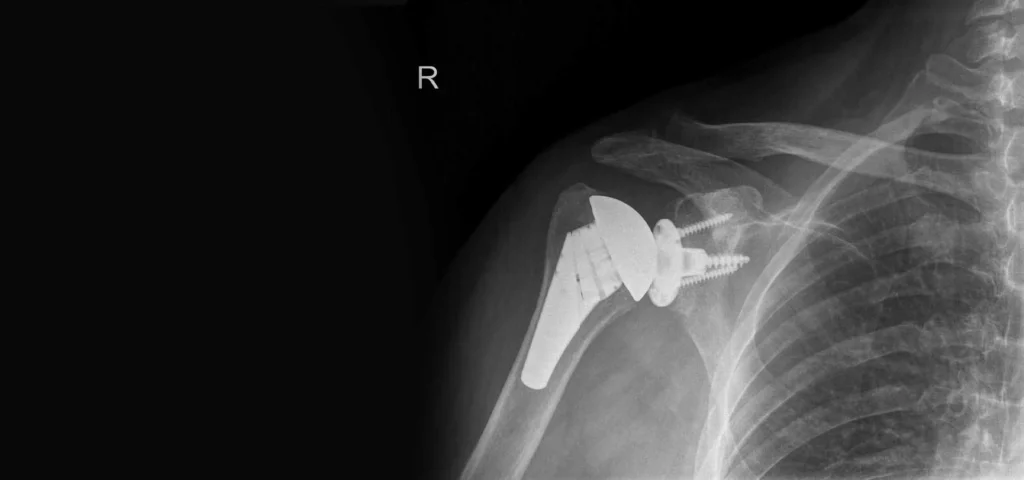

ολική αρθροπλαστική ώμου

Oλική Αρθροπλαστική Ώμου: Τι Είδους Προετοιμασία Χρειάζεται Πριν από την Επέμβαση

Η ολική αρθροπλαστική ώμου είναι μια σύνθετη επέμβαση που απαιτεί...